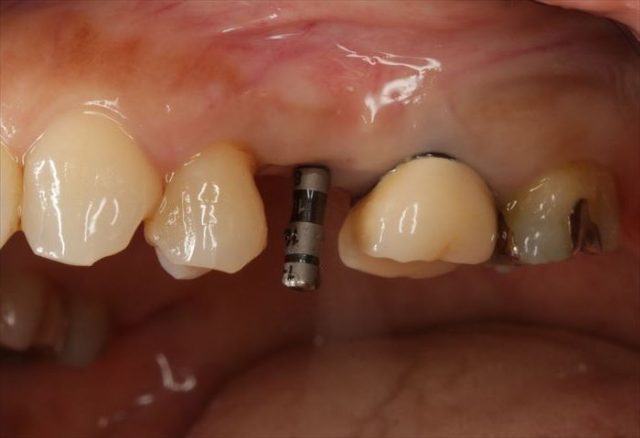

前後の歯も今後治療を進めていきますが、まだ手つかずの状態です。

この部分は抜歯とメタルタトゥーの切除を行った場所です。

挿入ジグを外しました。

封鎖スクリューでインプラントフィクスチャーを保護します。

フラップレス埋入オペでは出血もあまりありません。

無事に終わりました。